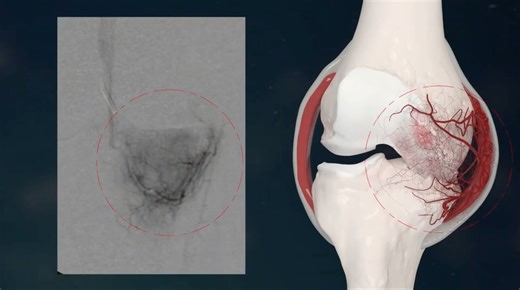

Arteriovenous Malformation (AVM)